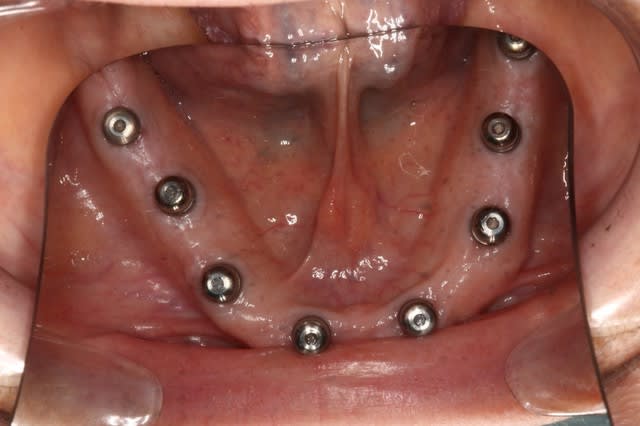

Exo + greffes + implants (axe et position idéaux, à la Misch) Planif 3D

(10 en haut et 8-10 en bas)

Bridges sur implants

Le même cas, patiente de 48 ans, paro ,mobilité, stellittes, occlusion moche, bref, rien de bon.

Bon j'aurais pu en placer 10 en bas...mais bon...